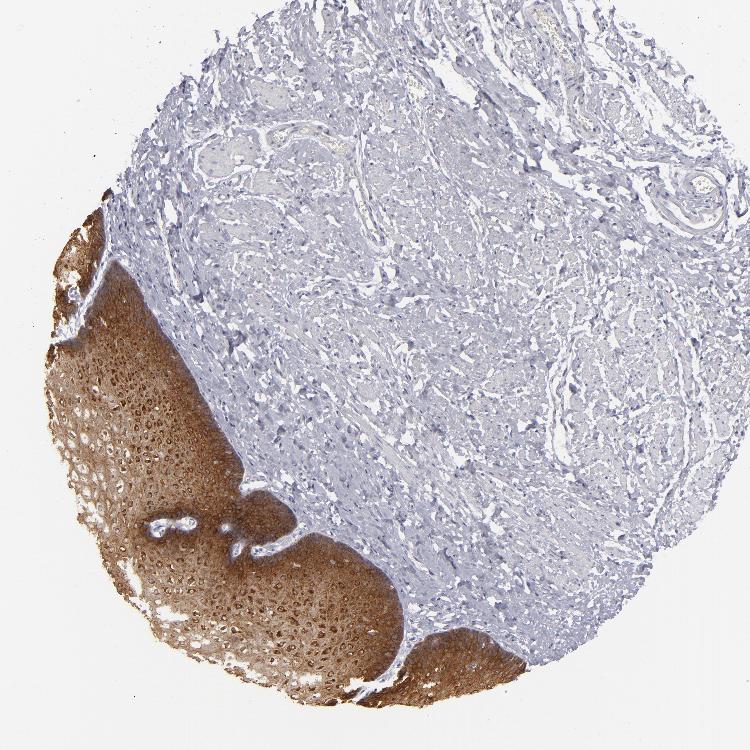

ESOPHAGUS - Antibody stainingi

Antibody staining in the annotated cell types in the current human tissue is reported as not detected, low, medium, or high, based on conventional immunohistochemistry profiling in selected tissues. This score is based on the combination of the staining intensity and fraction of stained cells.

Each image is clickable and will lead to virtual microscopy that enables deeper exploration of all samples and also displays staining intensity scores, fraction scores and subcellular localization as well as patient and tissue information for each sample.

Antibody HPA032047Antibody CAB002139

Squamous epithelial cells HighHigh